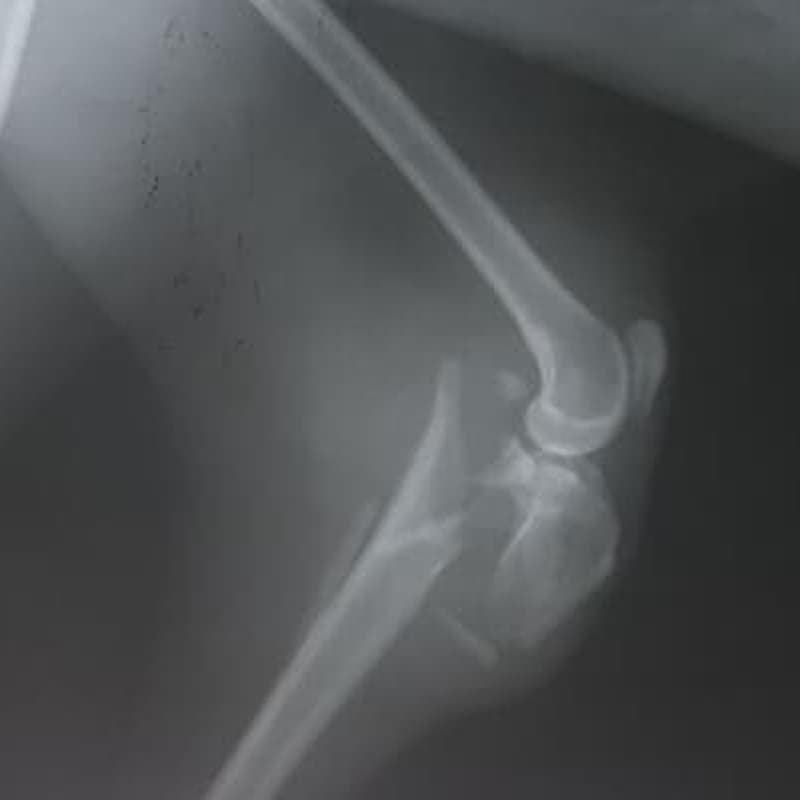

Cirugía